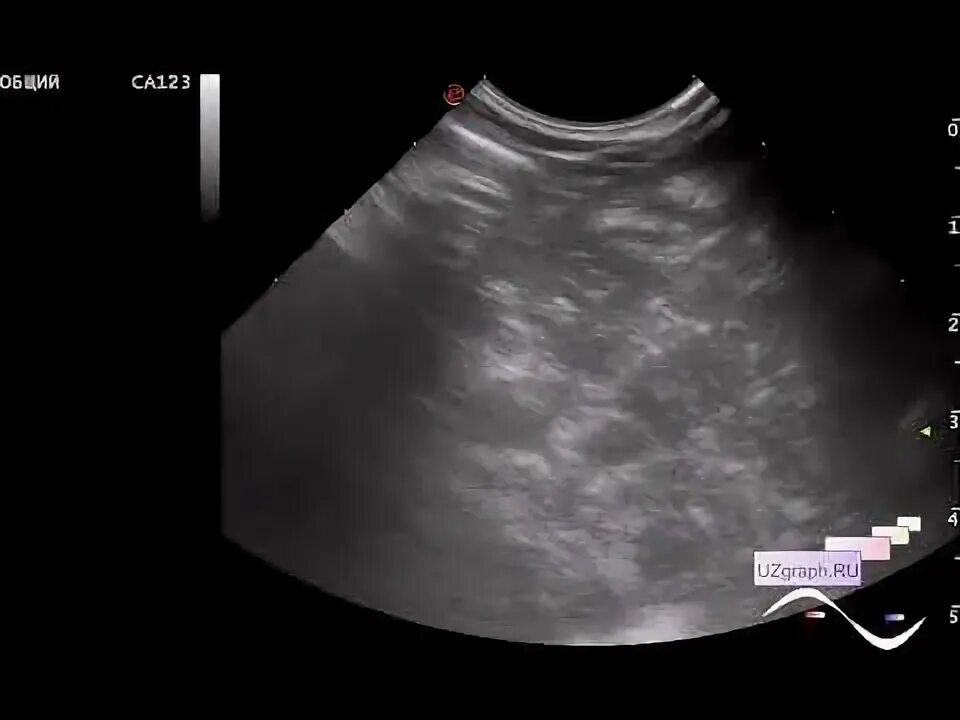

Паренхима диффузно неоднородная печени